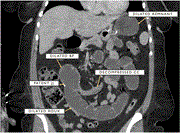

Distal jejunal gallstone ileus—an unusual cause of bowel obstruction: a case report

Munaser Alamoodi

Journal of Surgical Case Reports, Volume 2023, Issue 10, October 2023, rjad557, https://doi.org/10.1093/jscr/rjad557